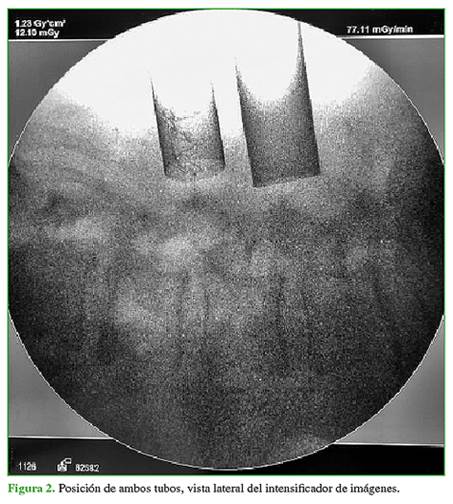

Se colocó al paciente en decúbito prono y se le administró anestesia general. Se utilizó radioscopia lateral para marcar la localización de la incisión cutánea. Ambos cirujanos establecen las incisiones de acuerdo con el nivel por tratar (Figura 2).